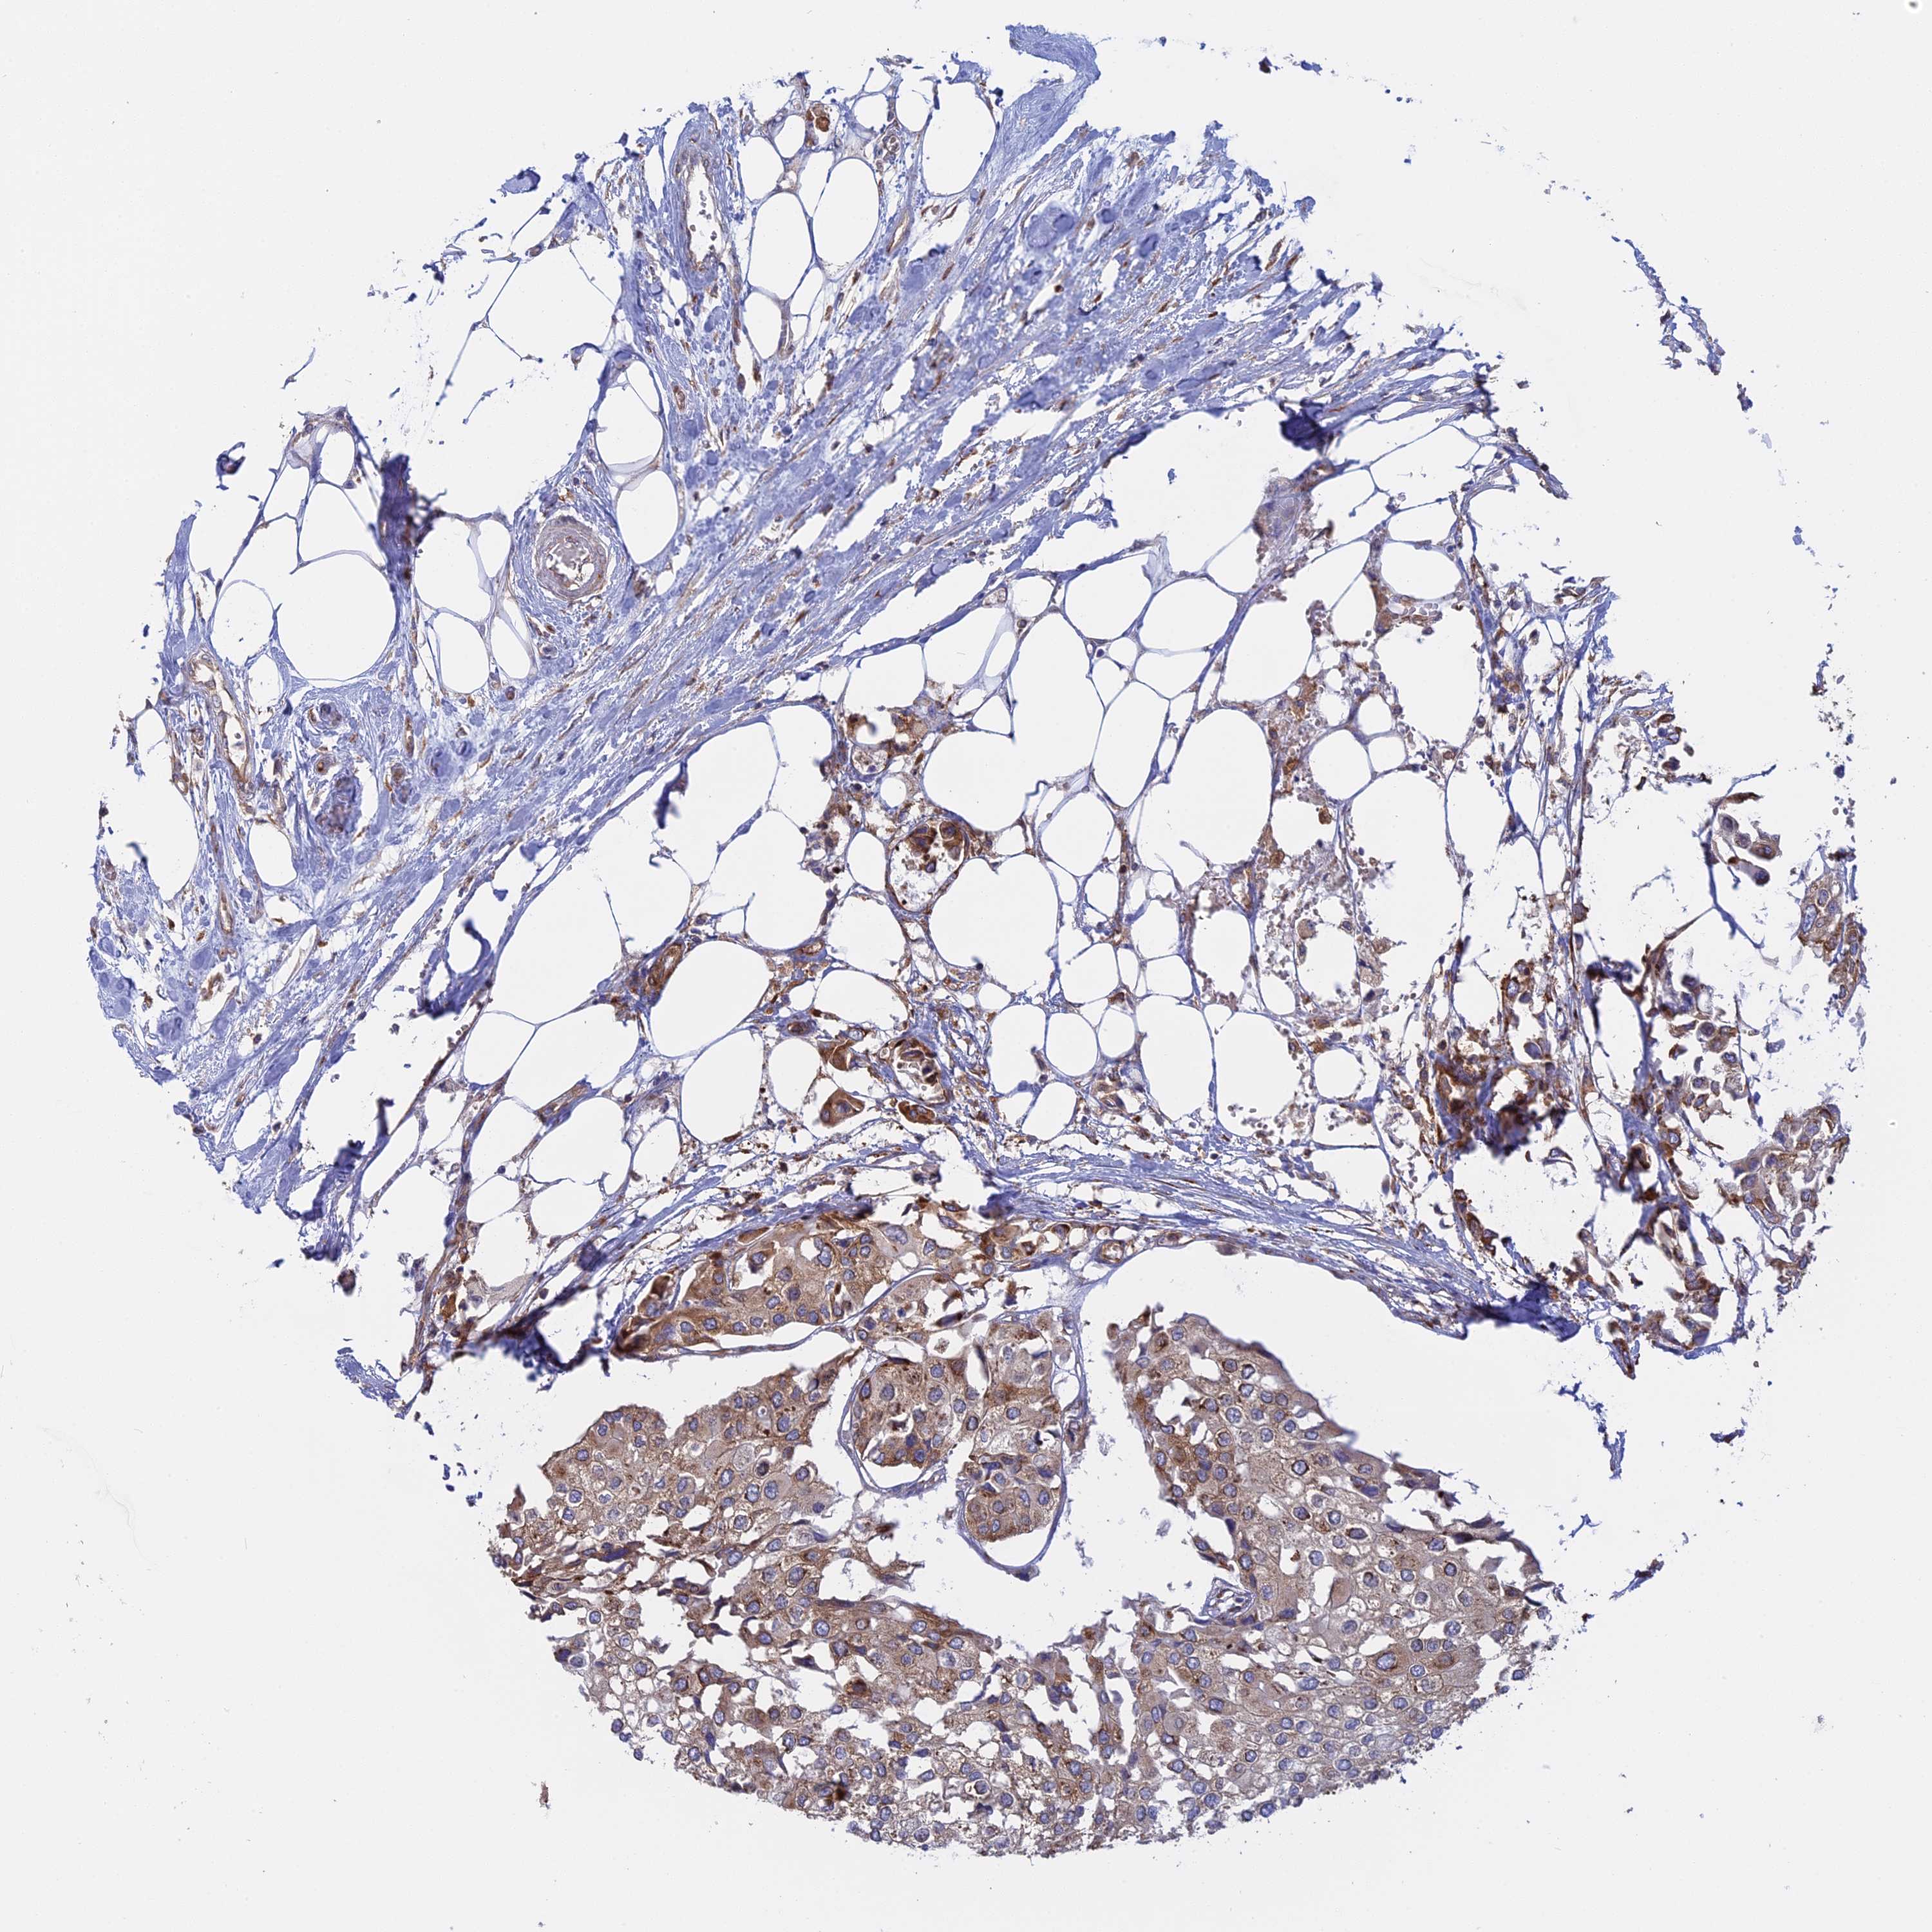

UROTHELIAL CANCER - Protein expressioni

A mouse-over function shows sample information and annotation data. Click on an image to view it in a full screen mode. Samples can be filtered based on level of antibody staining by selecting one or several of the following categories: high, medium, low and not detected. The assay and annotation is described here.

Note that samples used for immunohistochemistry by the Human Protein Atlas do not correspond to samples in the TCGA dataset.

Antibody stainingi

Antibody staining in the annotated cell types in the current human tissue is reported as not detected, low, medium, or high, based on conventional immunohistochemistry profiling in selected tissues. This score is based on the combination of the staining intensity and fraction of stained cells.

Each image is clickable and will lead to virtual microscopy that enables deeper exploration of all samples and also displays staining intensity scores, fraction scores and subcellular localization as well as patient and tissue information for each sample.

Antibody HPA042484

Antibody HPA045481

Staining

High

Medium

Low

Not detected

Intensity

Strong

Moderate

Weak

Negative

Quantity

>75%

75%-25%

<25%

None

Location

Nuclear

Cytoplasmic/membranous

Cytoplasmic/membranous,nuclear

Urothelial carcinoma, High grade

Urothelial carcinoma, Low grade

Urothelial carcinoma, NOS